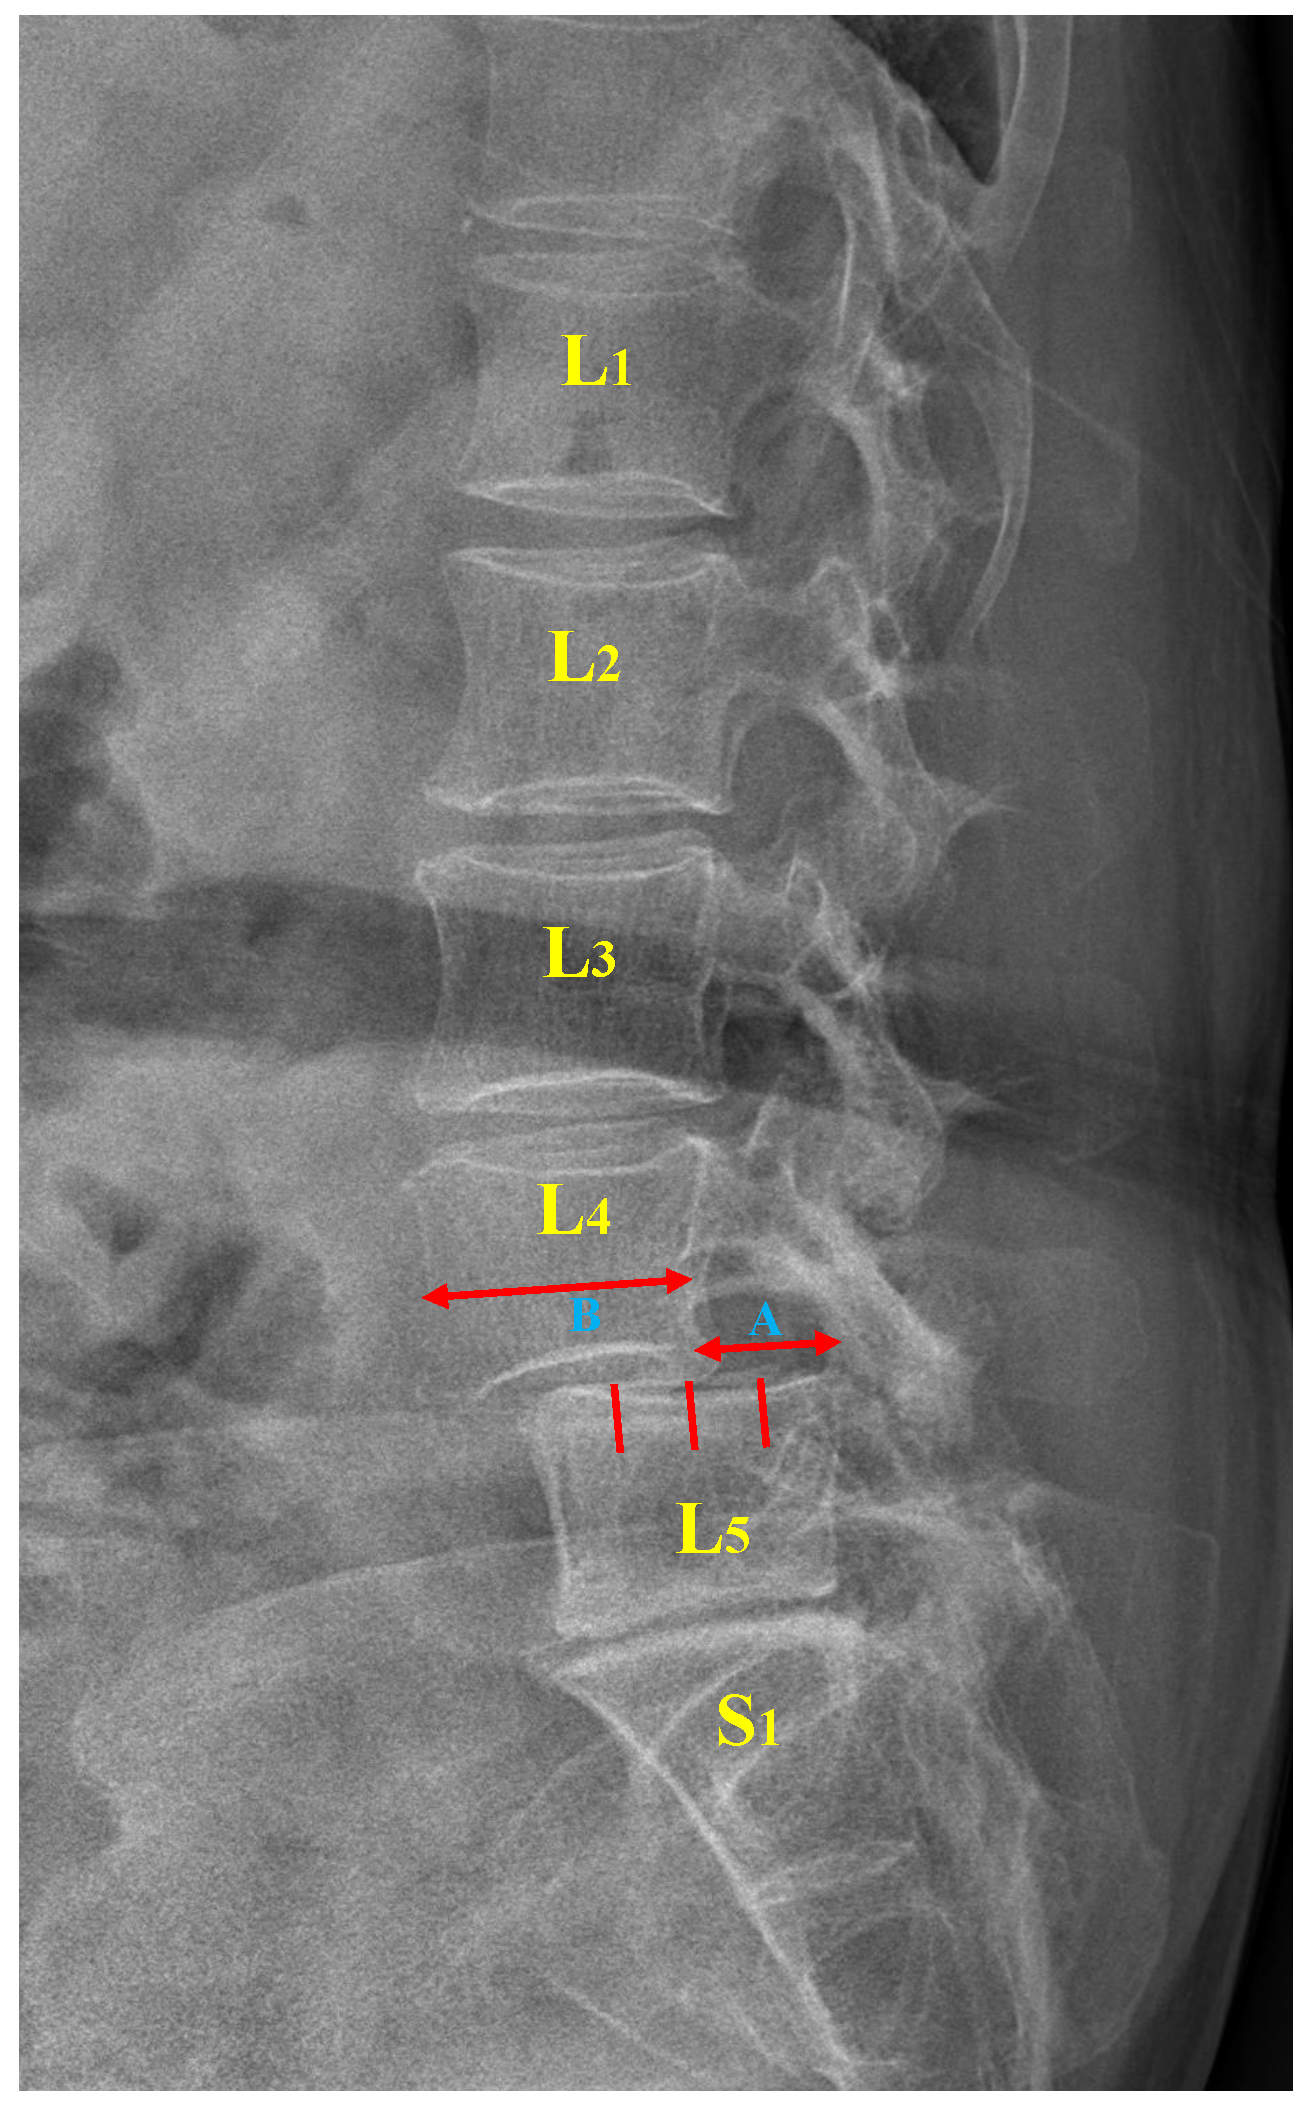

Moreover, the Meyerding classification with five variants is widely used in clinical practice and research owing to its simplicity and ease of application [7,11]. The degree of slippage is classified into five grades by evaluating the extent to which the superior vertebra is displaced relative to the inferior vertebra. Specifically, the ratio of the bare displacement value of the upper vertebra (A) to its width (B) is calculated to obtain a P-grade (as illustrated in Figure 1). Table 1 outlines the relationship between the P-grade and the degree of vertebral slippage. With 50% as the threshold, a P-grade that is either less or more than 50% corresponds to mild or severe slippage, respectively. Of note, a P-grade greater than 100% represents a complete vertebral slippage, the most serious presentation of the condition [12].

Figure 1.

Lumbar spondylolisthesis. L: lumbar vertebra, S: sacral vertebra, A: slip distance between two vertebrae, B: width of the superior vertebra.